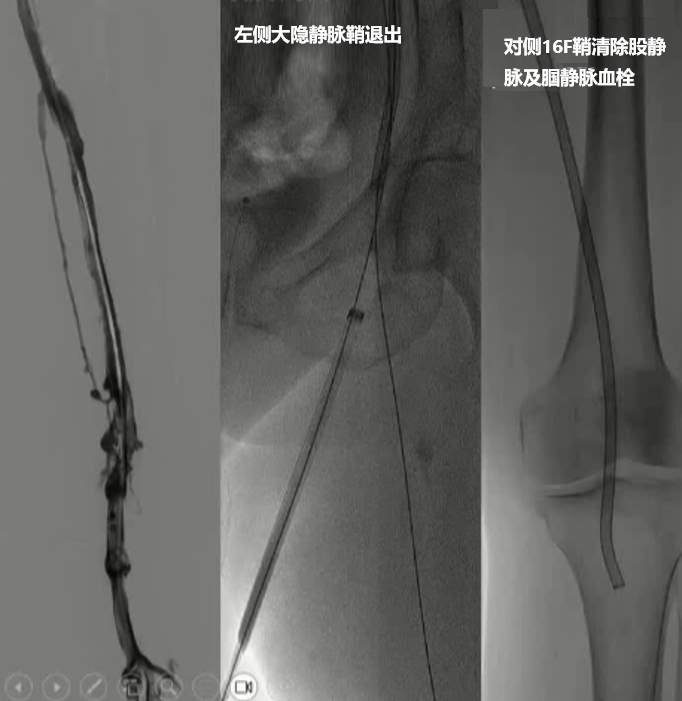

通过腘窝途径可处理同侧深部开口病变 经对侧途径进行深部/腘窝处操作

抽吸血栓:

将Indigo抽吸导管穿过导管鞘,直达血栓内部。启动抽吸泵,产生负压,将血栓吸入导管并收集到专用的血栓收集瓶中。同时,医生会操作分离器来优化抽吸效果。

评估与完成:

通过造影确认血栓已被成功清除,血流恢复后,撤出器械,手术结束。